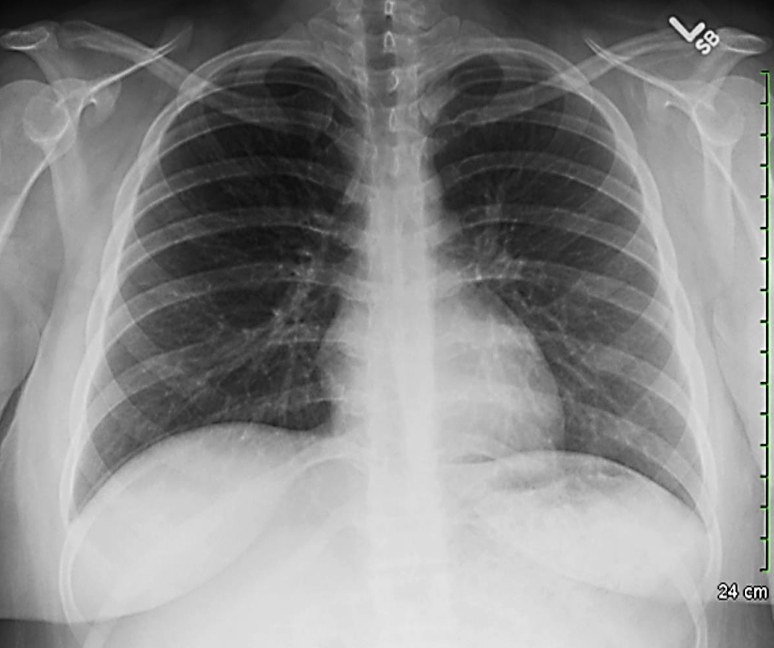

A 32 years old male presented with history of low grade fever, cough with sputum, sometimes blood stained. He has weight loss of 5 kg during this period. His chest X-Ray is shown ABOVE.

Describe the abnormality seen in the X-Ray?

- Cavitation and consolidation in the left upper lung

- bilateral Hilary lymphadenopathy

What is the likely diagnosis? Pulmonary TB

Mention 2 other investigations which you will advise?

- o Sputum culture and smear

- o IGRA

Mention 2 factors which increase the risk of this disease?

- HIV

- Chemotherapy

Mention 2 drugs used to treat this medical condition?

- o Rifampicin

- o INH (Isoniazid)